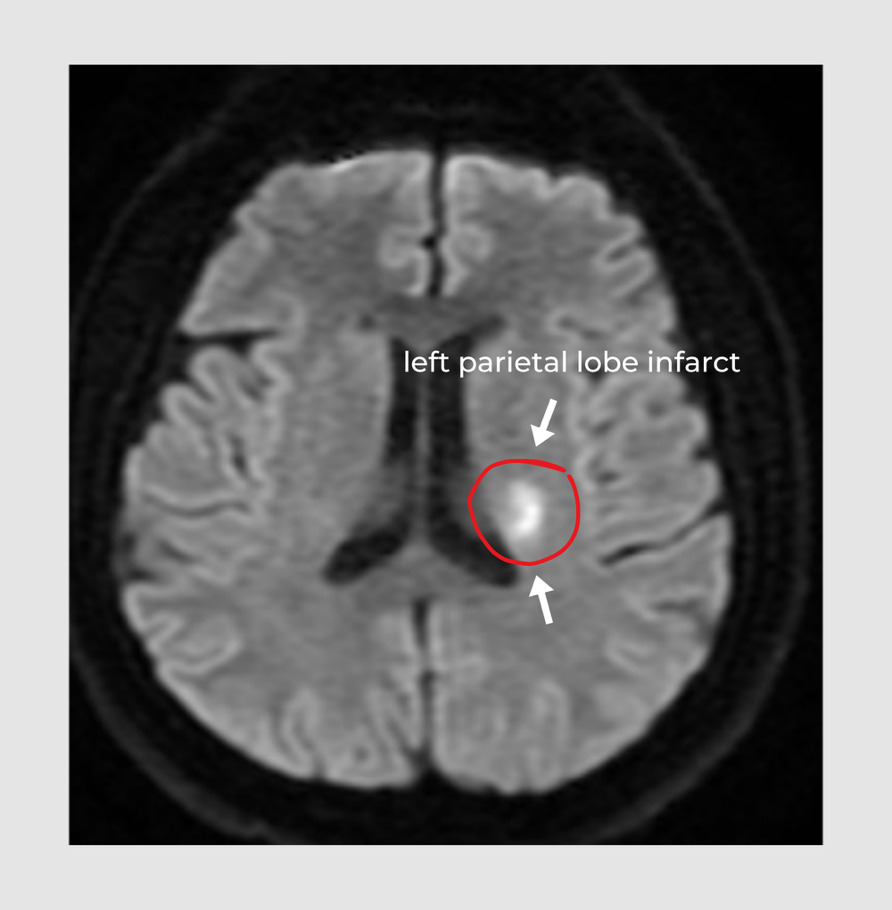

An acute left parietal infarct results from the sudden occlusion of blood flow to the left parietal lobe. The lack of blood in the left parietal lobe results in increasing damage to the tissues and neurons over time. This damage often presents as right-sided weakness, and/or difficulty performing motor tasks on the right hemisphere of the body.3 It may also present as language issues, such as slurred speech or stuttering.4,5 Some infarcts in the left parietal lobe can result in a disorder called Gerstmann Syndrome, which presents as difficulty in writing (agraphia), difficulty calculating basic math (acalculia), difficulty in identifying fingers (finger agnosia), and left-right disorientation.6,7 [Figure 1]. This was the case with our patient. Others may be associated with right-sided Alien Hand Syndrome (AHS), in which patients develop an estrangement from, and loss of motor control of a limb located on the right hemisphere of the patient’s body.8–10 Early detection of these symptoms leads to an early diagnosis and prompt treatment of stroke.

Subsequent magnetic resonance imaging (MRI) of the brain showed acute infarction of the left parietal lobe, displayed by the small white area [Figure 3].

The patient showed symptoms of right-sided arm and leg weakness and slurred speech. Additionally, he presented all four symptoms of Gerstmann Syndrome including agraphia, acalculia, finger agnosia, and left-right disorientation. Gerstmann Syndrome typically occurs when there is a lesion in the left parietal lobe (angular gyrus), and rarely in the right parietal.6,7 It was confirmed he had a left parietal infarct shown by a small white spot in the MRI scan. Although he had an infarct, he did not show any symptoms of Alien Hand Syndrome. Some factors that could be considered regarding the wide range of symptoms for a left parietal lobe infarct include the vast different structures (tissues, cells, neurons, etc.) corresponding with different functions that are damaged, the length of time since the left parietal lobe has been cut off from blood supply, and the size or extremity of the area affected.